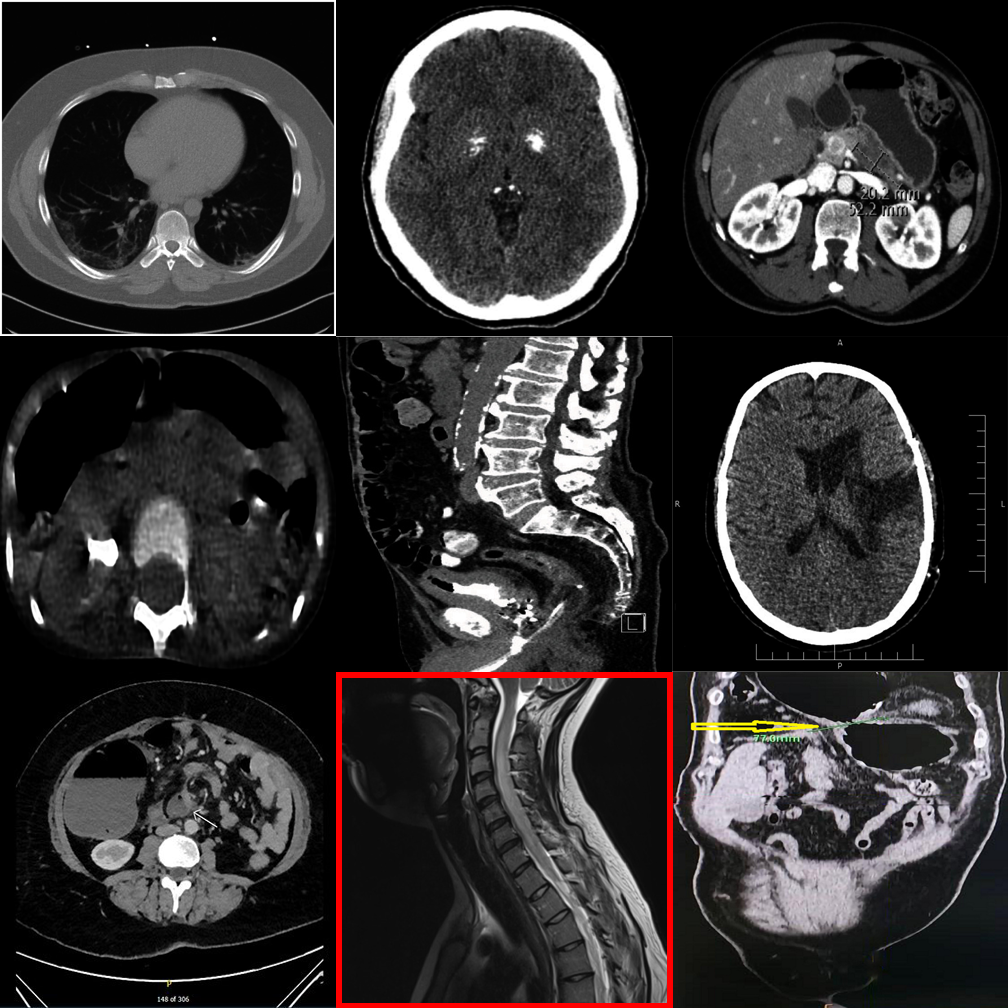

MedObvious abstracts multi-view clinical workflows into small grids where the model must identify an outlier — or correctly state that none exists.

Each tier introduces new complexity. Real examples from the benchmark are shown alongside each tier description.

Basic modality mismatches in 2×2 grids. E.g., one MRI scan among CT scans.

Broader modality pool with finer intra-class appearance variability in 2×2 grids.

Dense 3×3 grids with 8 distractors. Systematic comparison is essential.

Anatomy and viewpoint mismatches. E.g., one abdomen CT among chest X-rays.

High-saliency clinical failures: surgical hardware, fractures, gross pathology.